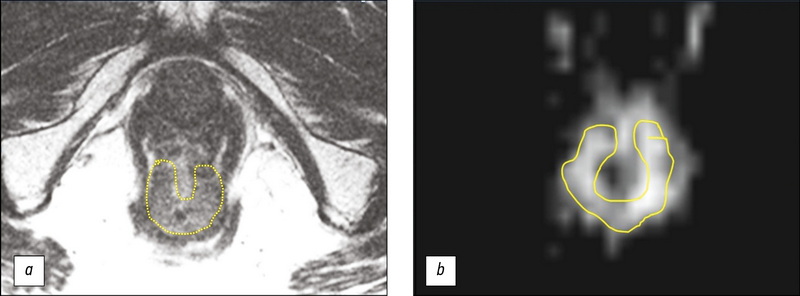

МРТ-оценка результата неоадъювантной химиолучевой терапии у больной раком прямой кишки, дополненная текстурным анализом Т2-ВИ опухоли (клинический случай)

В работе представлен клинический случай использования стратегии активного динамического наблюдения (watch & wait) у 73-летней больной раком нижнеампулярного отдела прямой кишки с хорошим ответом на неоадъювантную химиолучевую терапию. После трёх лет регулярного наблюдения, включающего пальцевое ректальное исследование, ректоскопию и магнитно-резонансную томографию (МРТ), указывавших на отсутствие прогрессирования опухоли, были получены результаты позитронно-эмиссионной томографии с 18F-фтордезоксиглюкозой, совмещённой с компьютерной томографией, выявившей в нижнеампулярном отделе прямой кишки участок гиперметаболической активности (SUVmax 27,1), в связи с чем было принято решение о проведении хирургического лечения. При обсуждении вопроса об объёме операции были учтены данные МРТ, дополненные результатами текстурного анализа Т2-ВИ, подтвердившие отсутствие прогрессирования. Пациентке было проведено органосохраняющее лечение в объёме трансанальной резекции опухоли. Патоморфологическое исследование операционного препарата установило воспалительные изменения в стенке кишки и отсутствие опухоли. Данный случай демонстрирует эффективность стандартного объёма обследования при использовании стратегии watch & wait и возможность использования текстурного анализа Т2-ВИ для повышения надежности МРТ-оценки ответа опухоли на химиолучевую терапию.